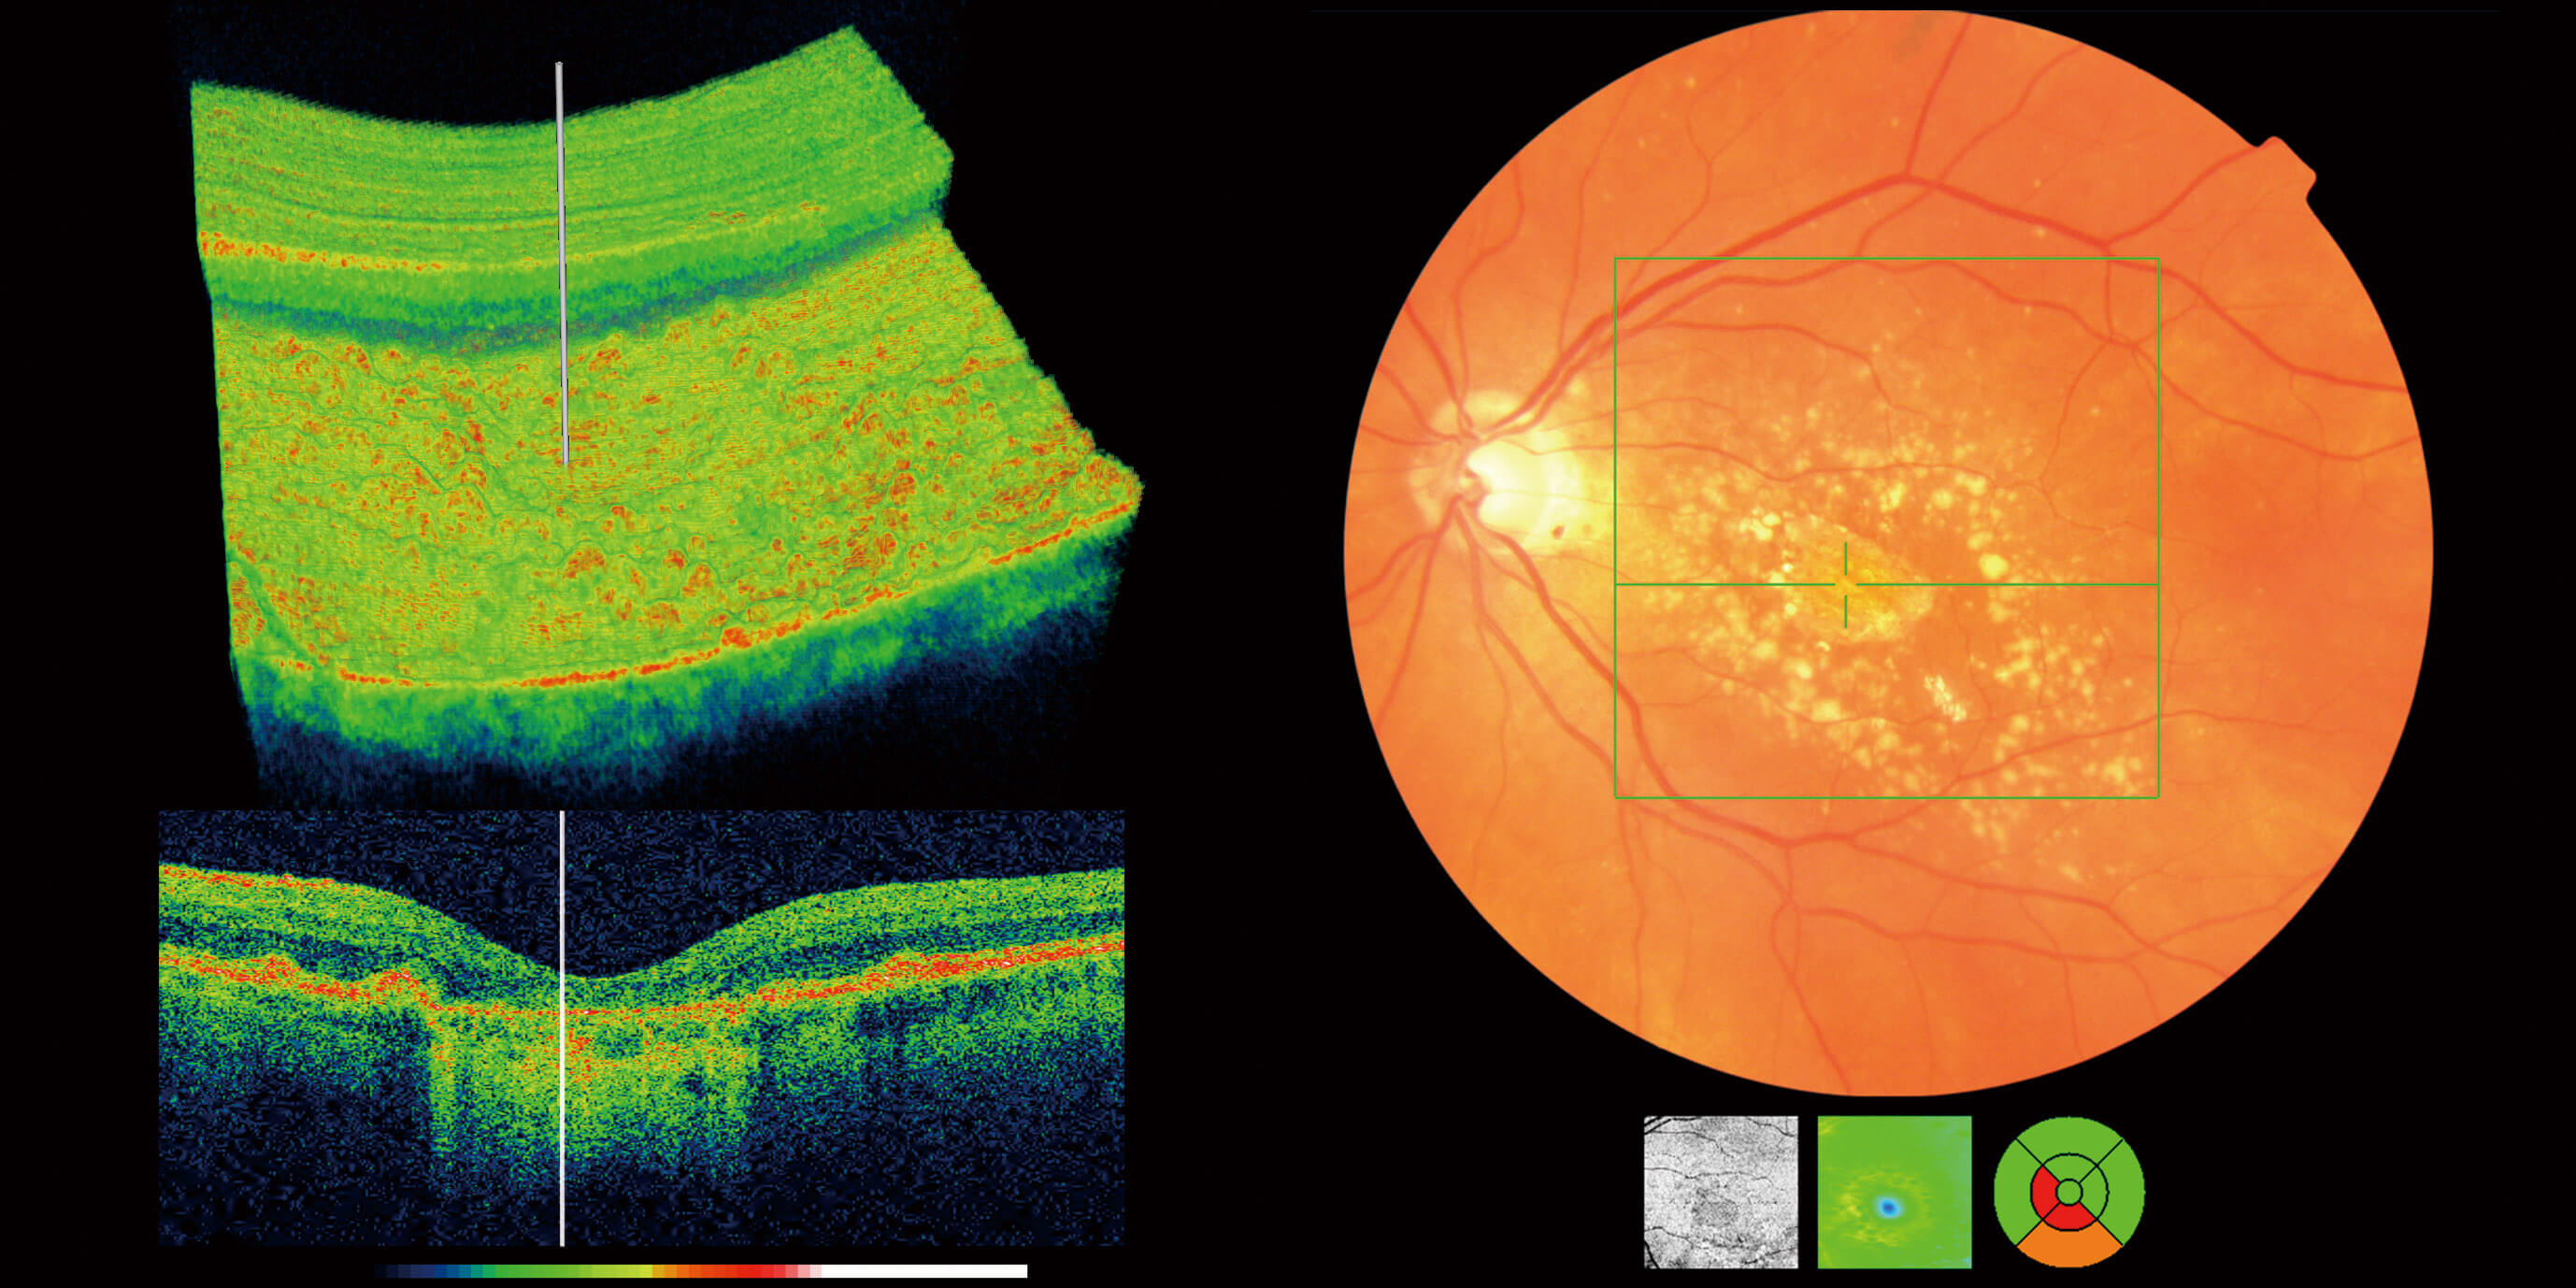

Optical Coherence Tomography (OCT) is an advanced eye scan, similar to ultrasound. The OCT uses light rather than sound waves to illustrate the different layers that make up the back of the eye. Within 2 seconds, the OCT takes over 30,000 individual scans of the back of the eye and this is used to produce a 3D image of the retina and optic nerve. The scan gives an accurate cross-sectional map through the retina and allows examination of the back of the eye in incredibly fine detail.

The OCT also captures a digital photograph of the surface of the eye at the same time, and this can then be cross-referenced with any areas of concern.

The scan shows us beneath the surface of your retina, so we can see and better understand the very fine changes which can be indications of something unhealthy or abnormal.

You will also get to see an instant 3D high definition image of your eyes.